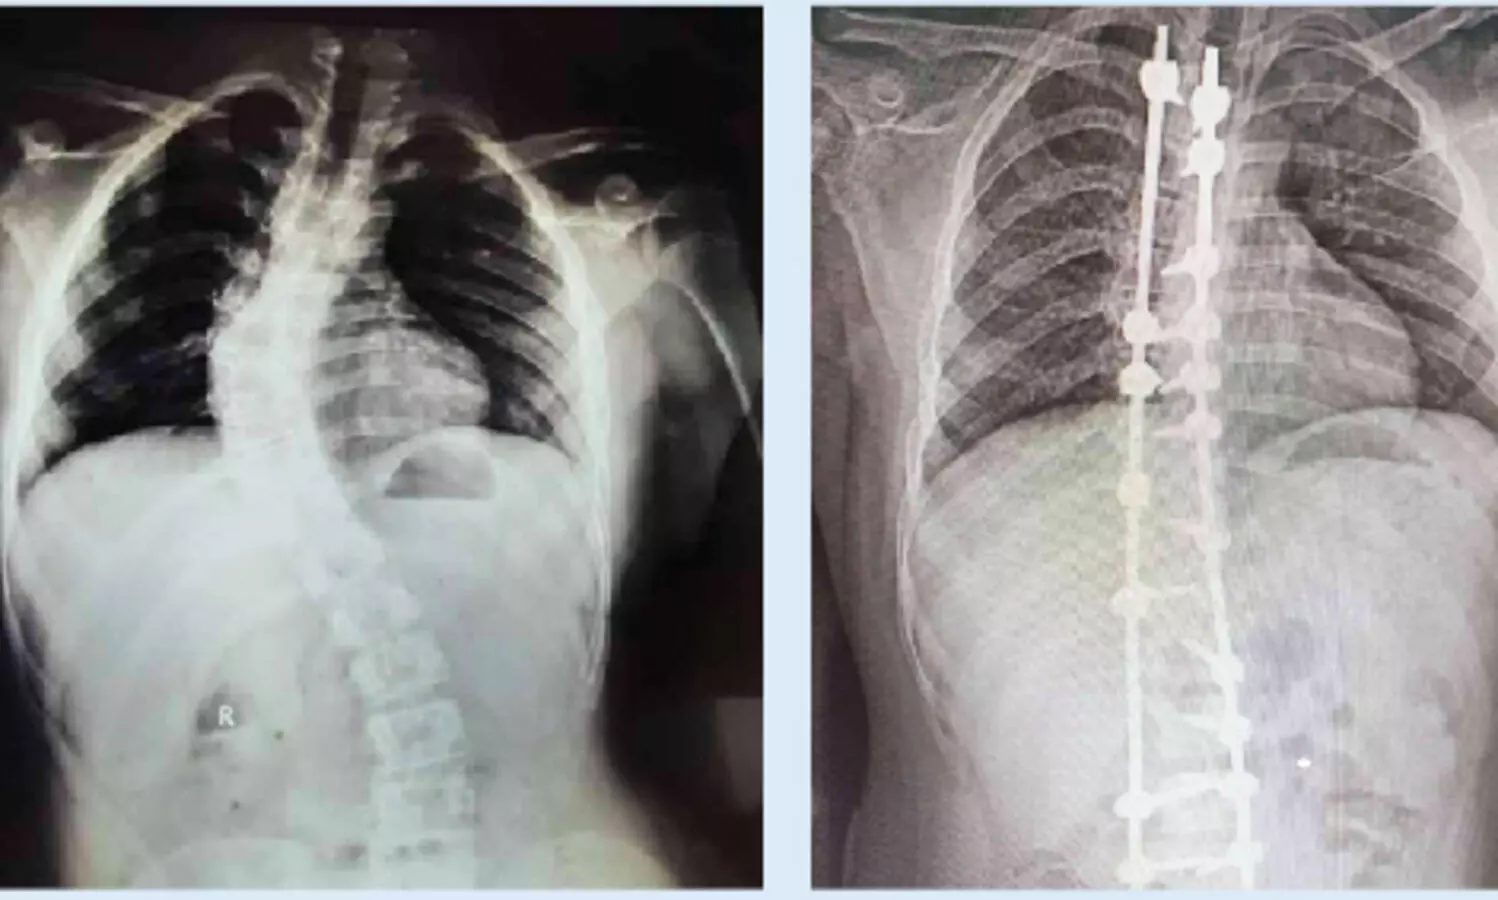

ഗവ. മെഡിക്കൽ കോളജ് ആശുപത്രിയിൽ നട്ടെല്ല് നിവർത്തുന്ന ശസ്ത്രക്രിയ